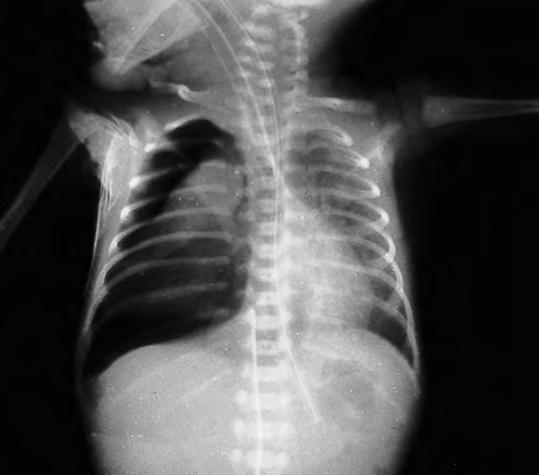

Parálisis diafragmática

Se presenta aislada en la cuarta parte de los casos o bien acompañando a la braquial en el 75% de los casos. Es motivada por afectación del nervio frénico que tiene su origen en las III, IV y V raíces cervicales. Se produce estiramiento en los partos podálicos, pero también puede observarse en el cefálico, con distocia de hombros. Es de preferencia derecha y unilateral, lo que hace que a veces pase desapercibida, cuando no se asocia a parálisis braquial. El diagnóstico se comprueba mediante la exploración radiológica y debe efectuarse a todo niño afecto de parálisis braquial; se observa el diafragma del lado afecto elevado y el signo de Kiemboek típico (movimiento paradójico) de la parálisis diafragmática. La ecografía en tiempo real dentro de la unidad neonatal se emplea para el diagnóstico en los niños muy pequeños. En las parálisis bilaterales el trastorno respiratorio es muy importante, con disnea, cianosis y depresión del hueco epigástrico en los movimientos inspiratorios. Como en otras parálisis obstétricas, existe la posibilidad de regresión sin tratamiento en pocos días. Si persiste durante más de dos meses planteará problemas de diagnóstico diferencial con la relajación diafragmática, de la que muchas veces es imposible de deslindar, aun con estudios anatomopatológicos.

Tratamiento. En las formas con dificultad respiratoria comprende el empleo de cuna basculante o presión positiva continua o intermitente según la gravedad. La colocación de los brazos por encima de la cabeza mejora la ventilación. En los casos muy graves (distrés respiratorio importante, neumonías de repetición, grave afectación del estado general) o rebeldes (persistencia clínica y radiológica) se considerará la intervención quirúrgica mediante plicatura del diafragma o colocación de marcapasos frénico.